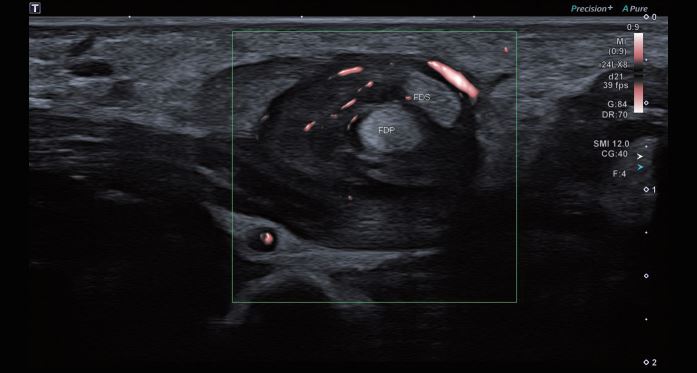

Зображення 2 Поперечна томограма тієї ж ділянки показує

FDP і FDS у поперечному перерізі з навколишніми

змінами люмбальних м'язів.